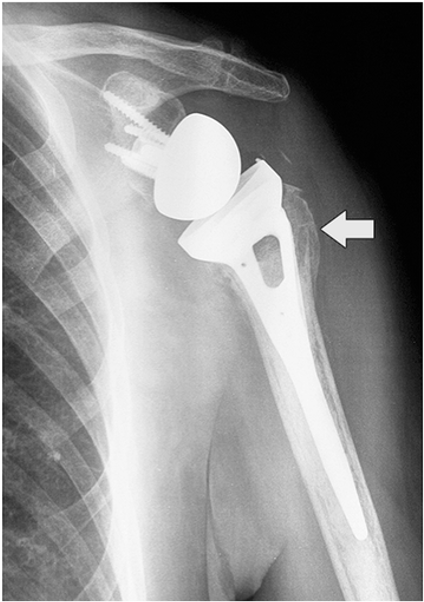

Prosthesis